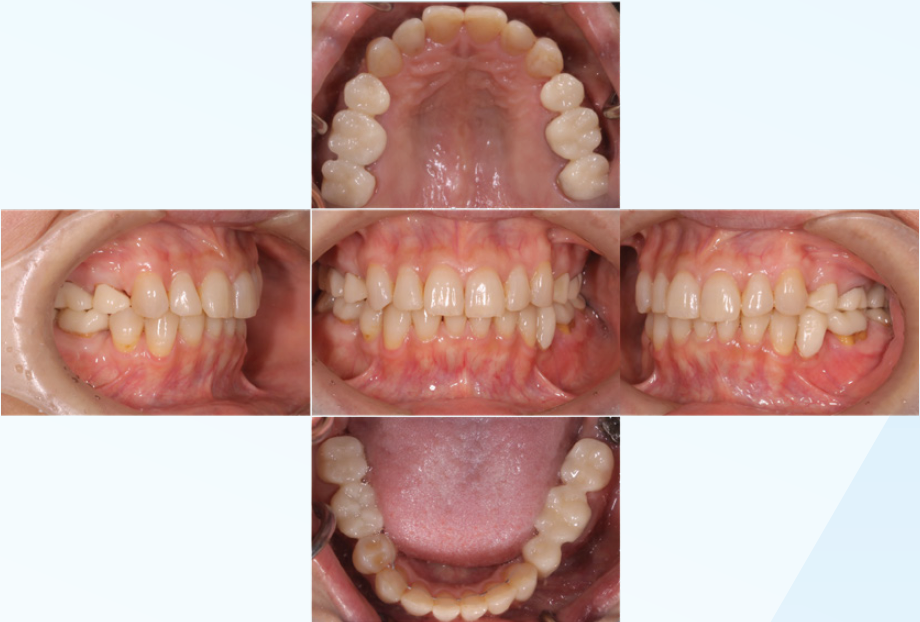

< 動的矯正終了時口腔内写真>

(図22)

前歯部にも嵌合が見られ、ミューチュアリー・プロテクテッド・オクリュージョンが

可能な口腔内に環境改善出来たことを確認

顎位安定のため適正なオクルーザルストップ付与が可能な

プロビジョナル・レストレーションを装着する